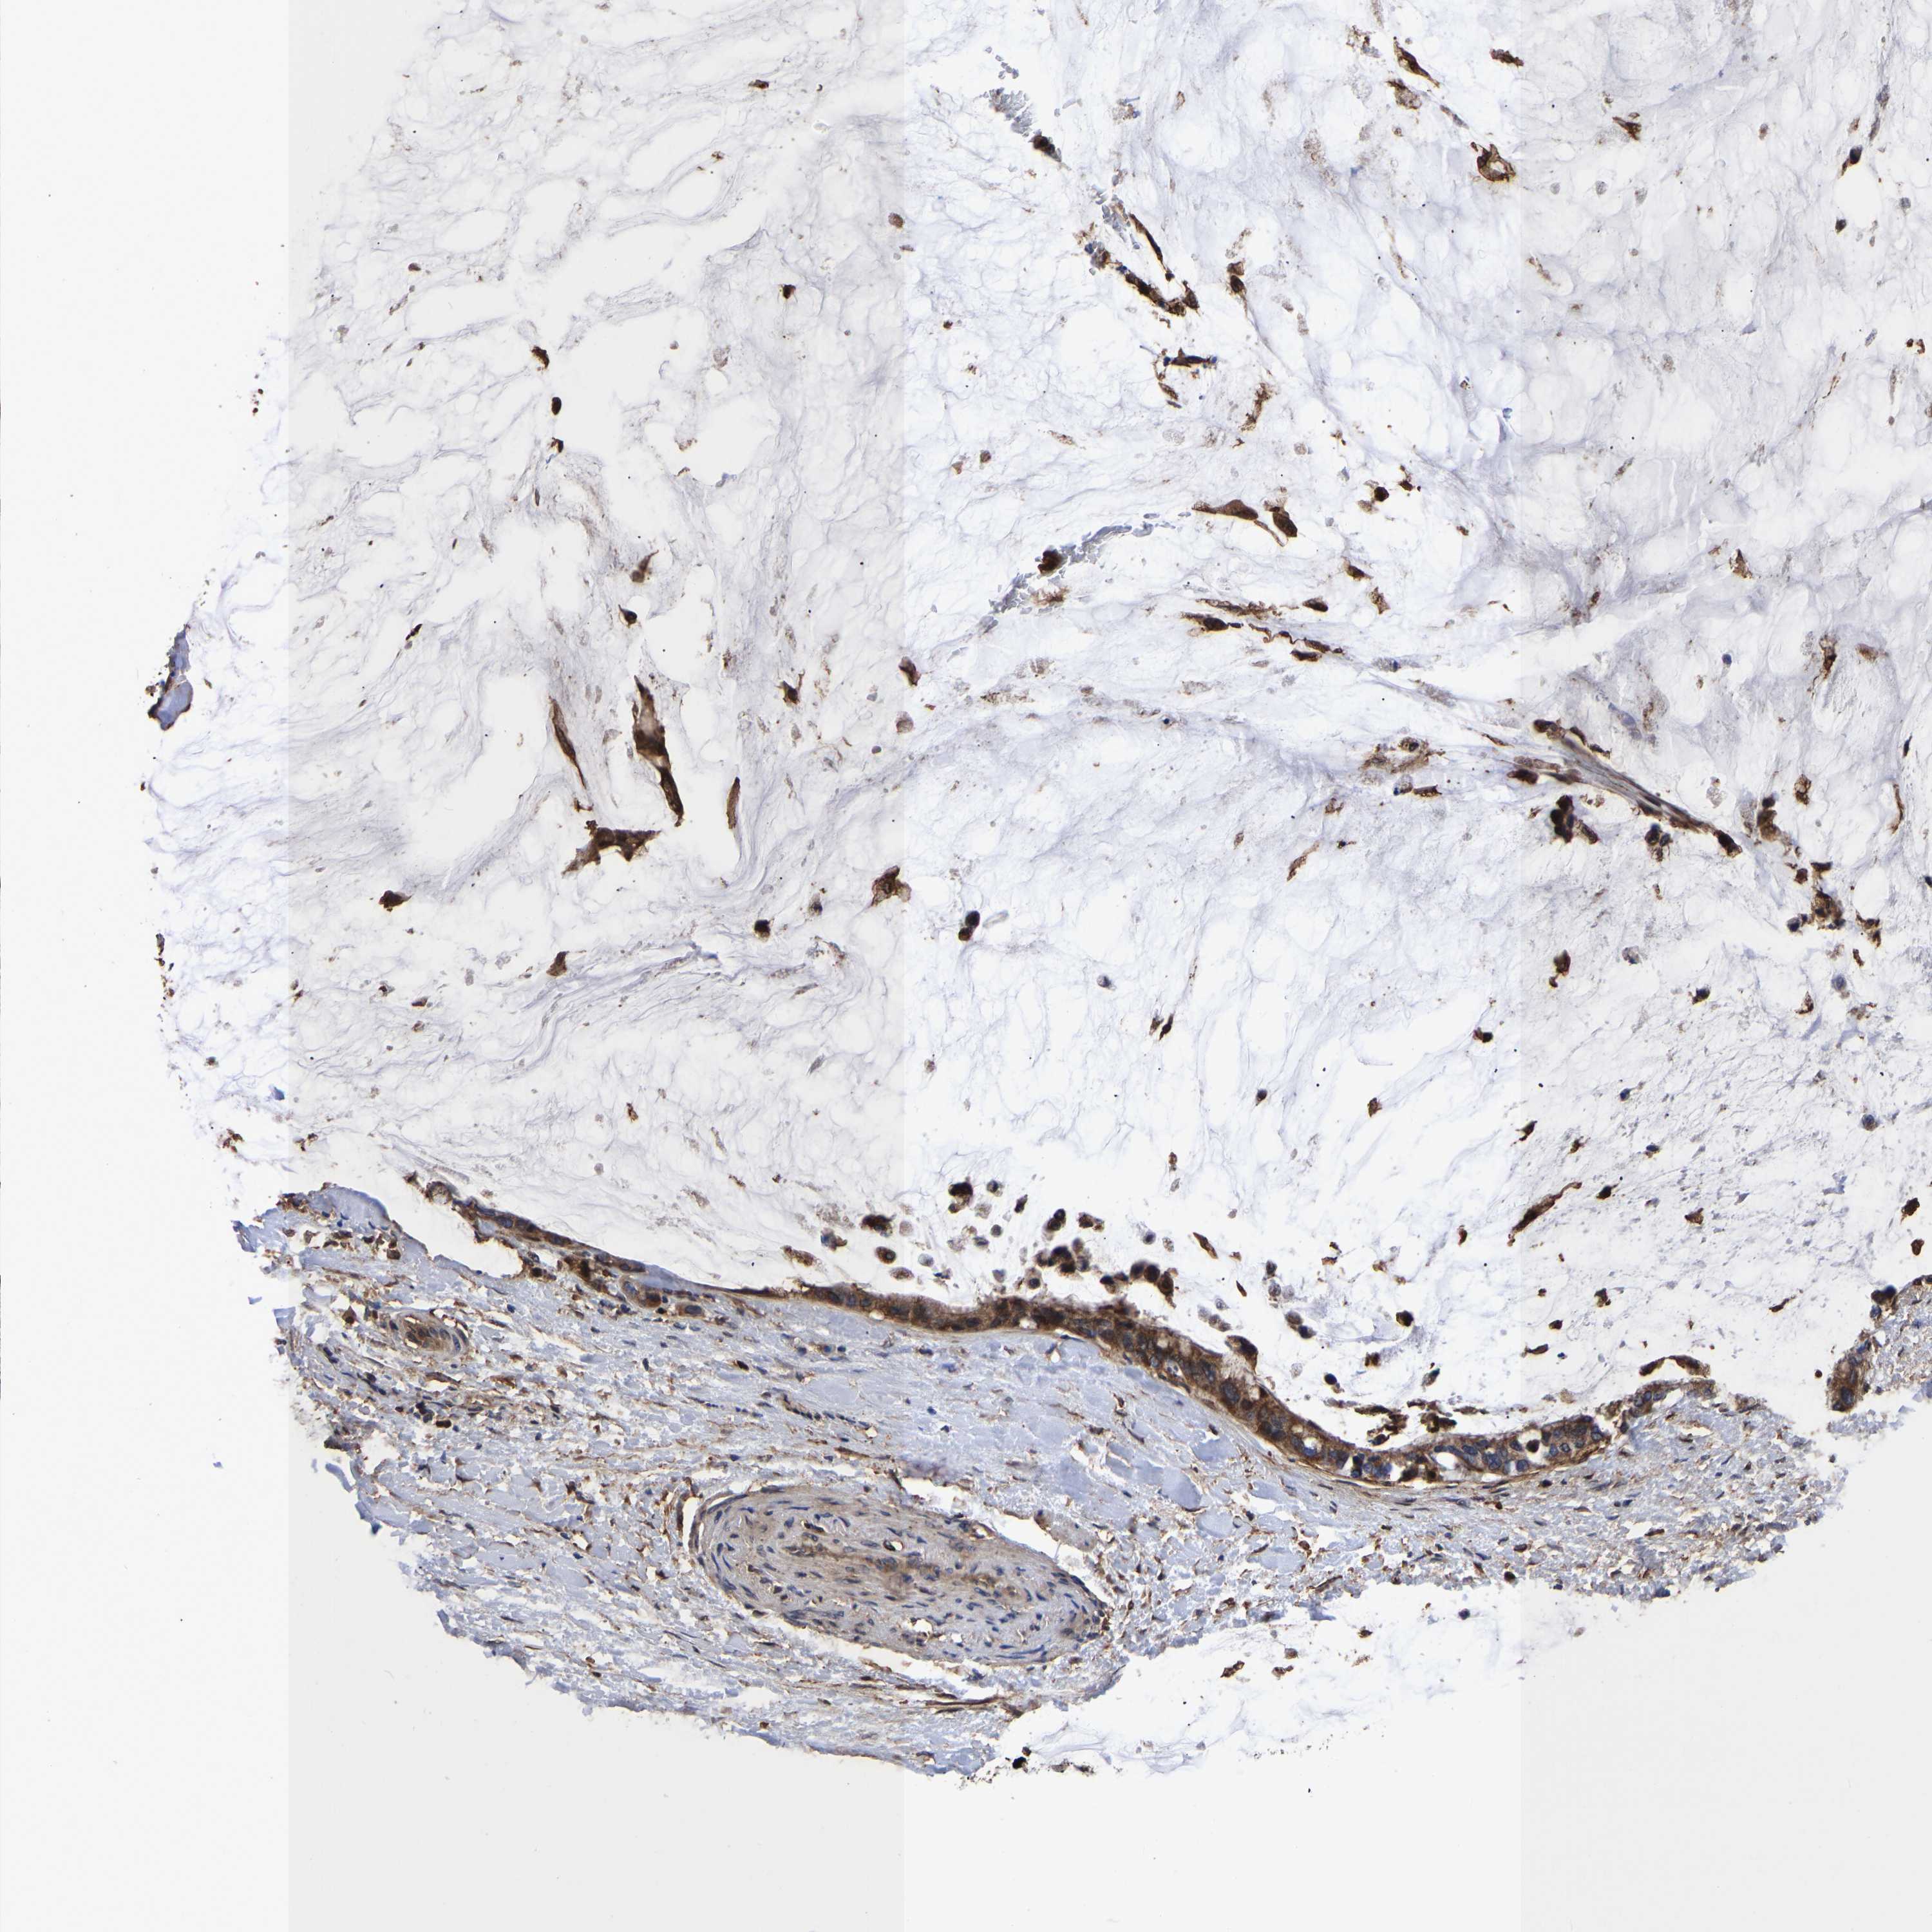

PANCREATIC CANCER - Protein expressioni

A mouse-over function shows sample information and annotation data. Click on an image to view it in a full screen mode. Samples can be filtered based on level of antibody staining by selecting one or several of the following categories: high, medium, low and not detected. The assay and annotation is described here.

Note that samples used for immunohistochemistry by the Human Protein Atlas do not correspond to samples in the TCGA dataset.

Antibody stainingi

Antibody staining in the annotated cell types in the current human tissue is reported as not detected, low, medium, or high, based on conventional immunohistochemistry profiling in selected tissues. This score is based on the combination of the staining intensity and fraction of stained cells.

Each image is clickable and will lead to virtual microscopy that enables deeper exploration of all samples and also displays staining intensity scores, fraction scores and subcellular localization as well as patient and tissue information for each sample.

Antibody HPA018844

Staining

High

Medium

Low

Not detected

Intensity

Strong

Moderate

Weak

Negative

Quantity

>75%

75%-25%

<25%

None

Location

Nuclear

Cytoplasmic/membranous

Cytoplasmic/membranous,nuclear

Adenocarcinoma, NOS